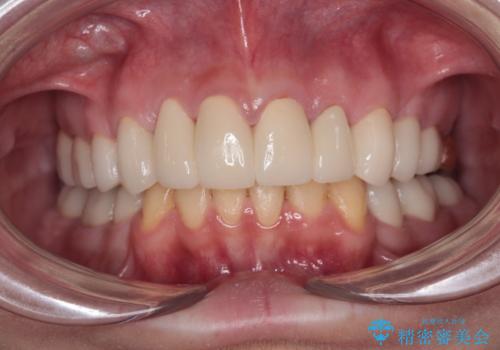

矯正治療終了後に、残った歯をオールセラミッククラウンにて補綴治療を行うこととしました。

途中来院が困難な時期があったり、歯周外科処置を行って治癒を待ったりと、治療期間は長くなりましたが、初診時とは比べものにならないくらいきれいに仕上げることができました。